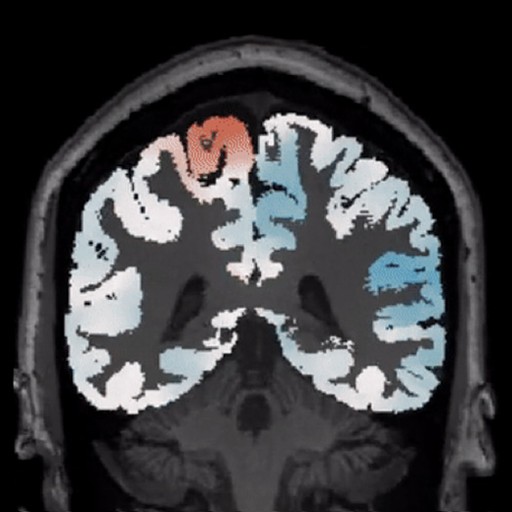

Analysis. Whole-brain morphometric mapping reveals deviation patterns across cortical and subcortical structures

Diagnostics. AI-powered lesion identification combined with expert radiologist validation delivers comprehensive case reports

BrainScores was built specifically for epilepsy surgery. Generic neuroimaging platforms serve multiple conditions but lack the depth required for focal cortical dysplasia detection

BrainScores was built exclusively for epilepsy surgery. Generic neuroimaging platforms serve multiple conditions but lack the depth required for focal cortical dysplasia detection.